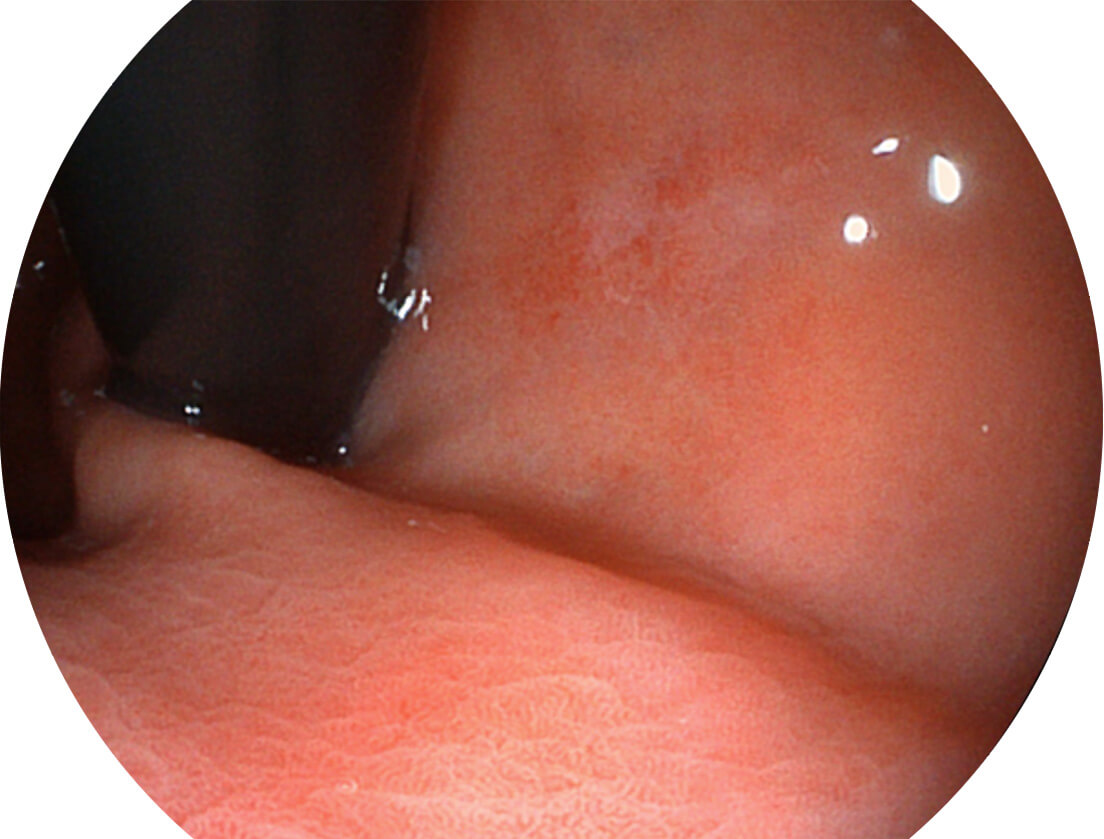

Spectral Focused lmaging, SFI

图像具有高亮度、高黏膜血管颜色对比度的特点,且不改变粘液、食物残渣、粪便的基本颜色,可在中远景下进行观察,助力消化道早期疾病的诊断。

白光图像

SFI图像